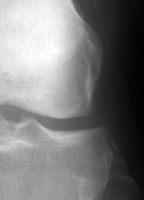

Frontal radiographs of the knee which reveal a small fleck of bone adjacent to the lateral aspect of the lateral tibial plateau. This "lateral capsular sign" is a simple radiographic finding visible on the routine AP knee x-ray, which indicates severe lateral capsular injury and should alert the examiner to the possibility of ACL tear. The fleck of bone represents an avulsion of the meniscotibial portion of the middle one-third of the lateral capsular ligament. It most commonly implies a disruption of the capsular ligament and the ACL. A-B Radiographs. C. MRI confirms the diagnosis of ACL tear.

AP knee - Click on the image for a larger versionAAP knee - Click on the image for a larger versionB - Click on the image for a larger versionC